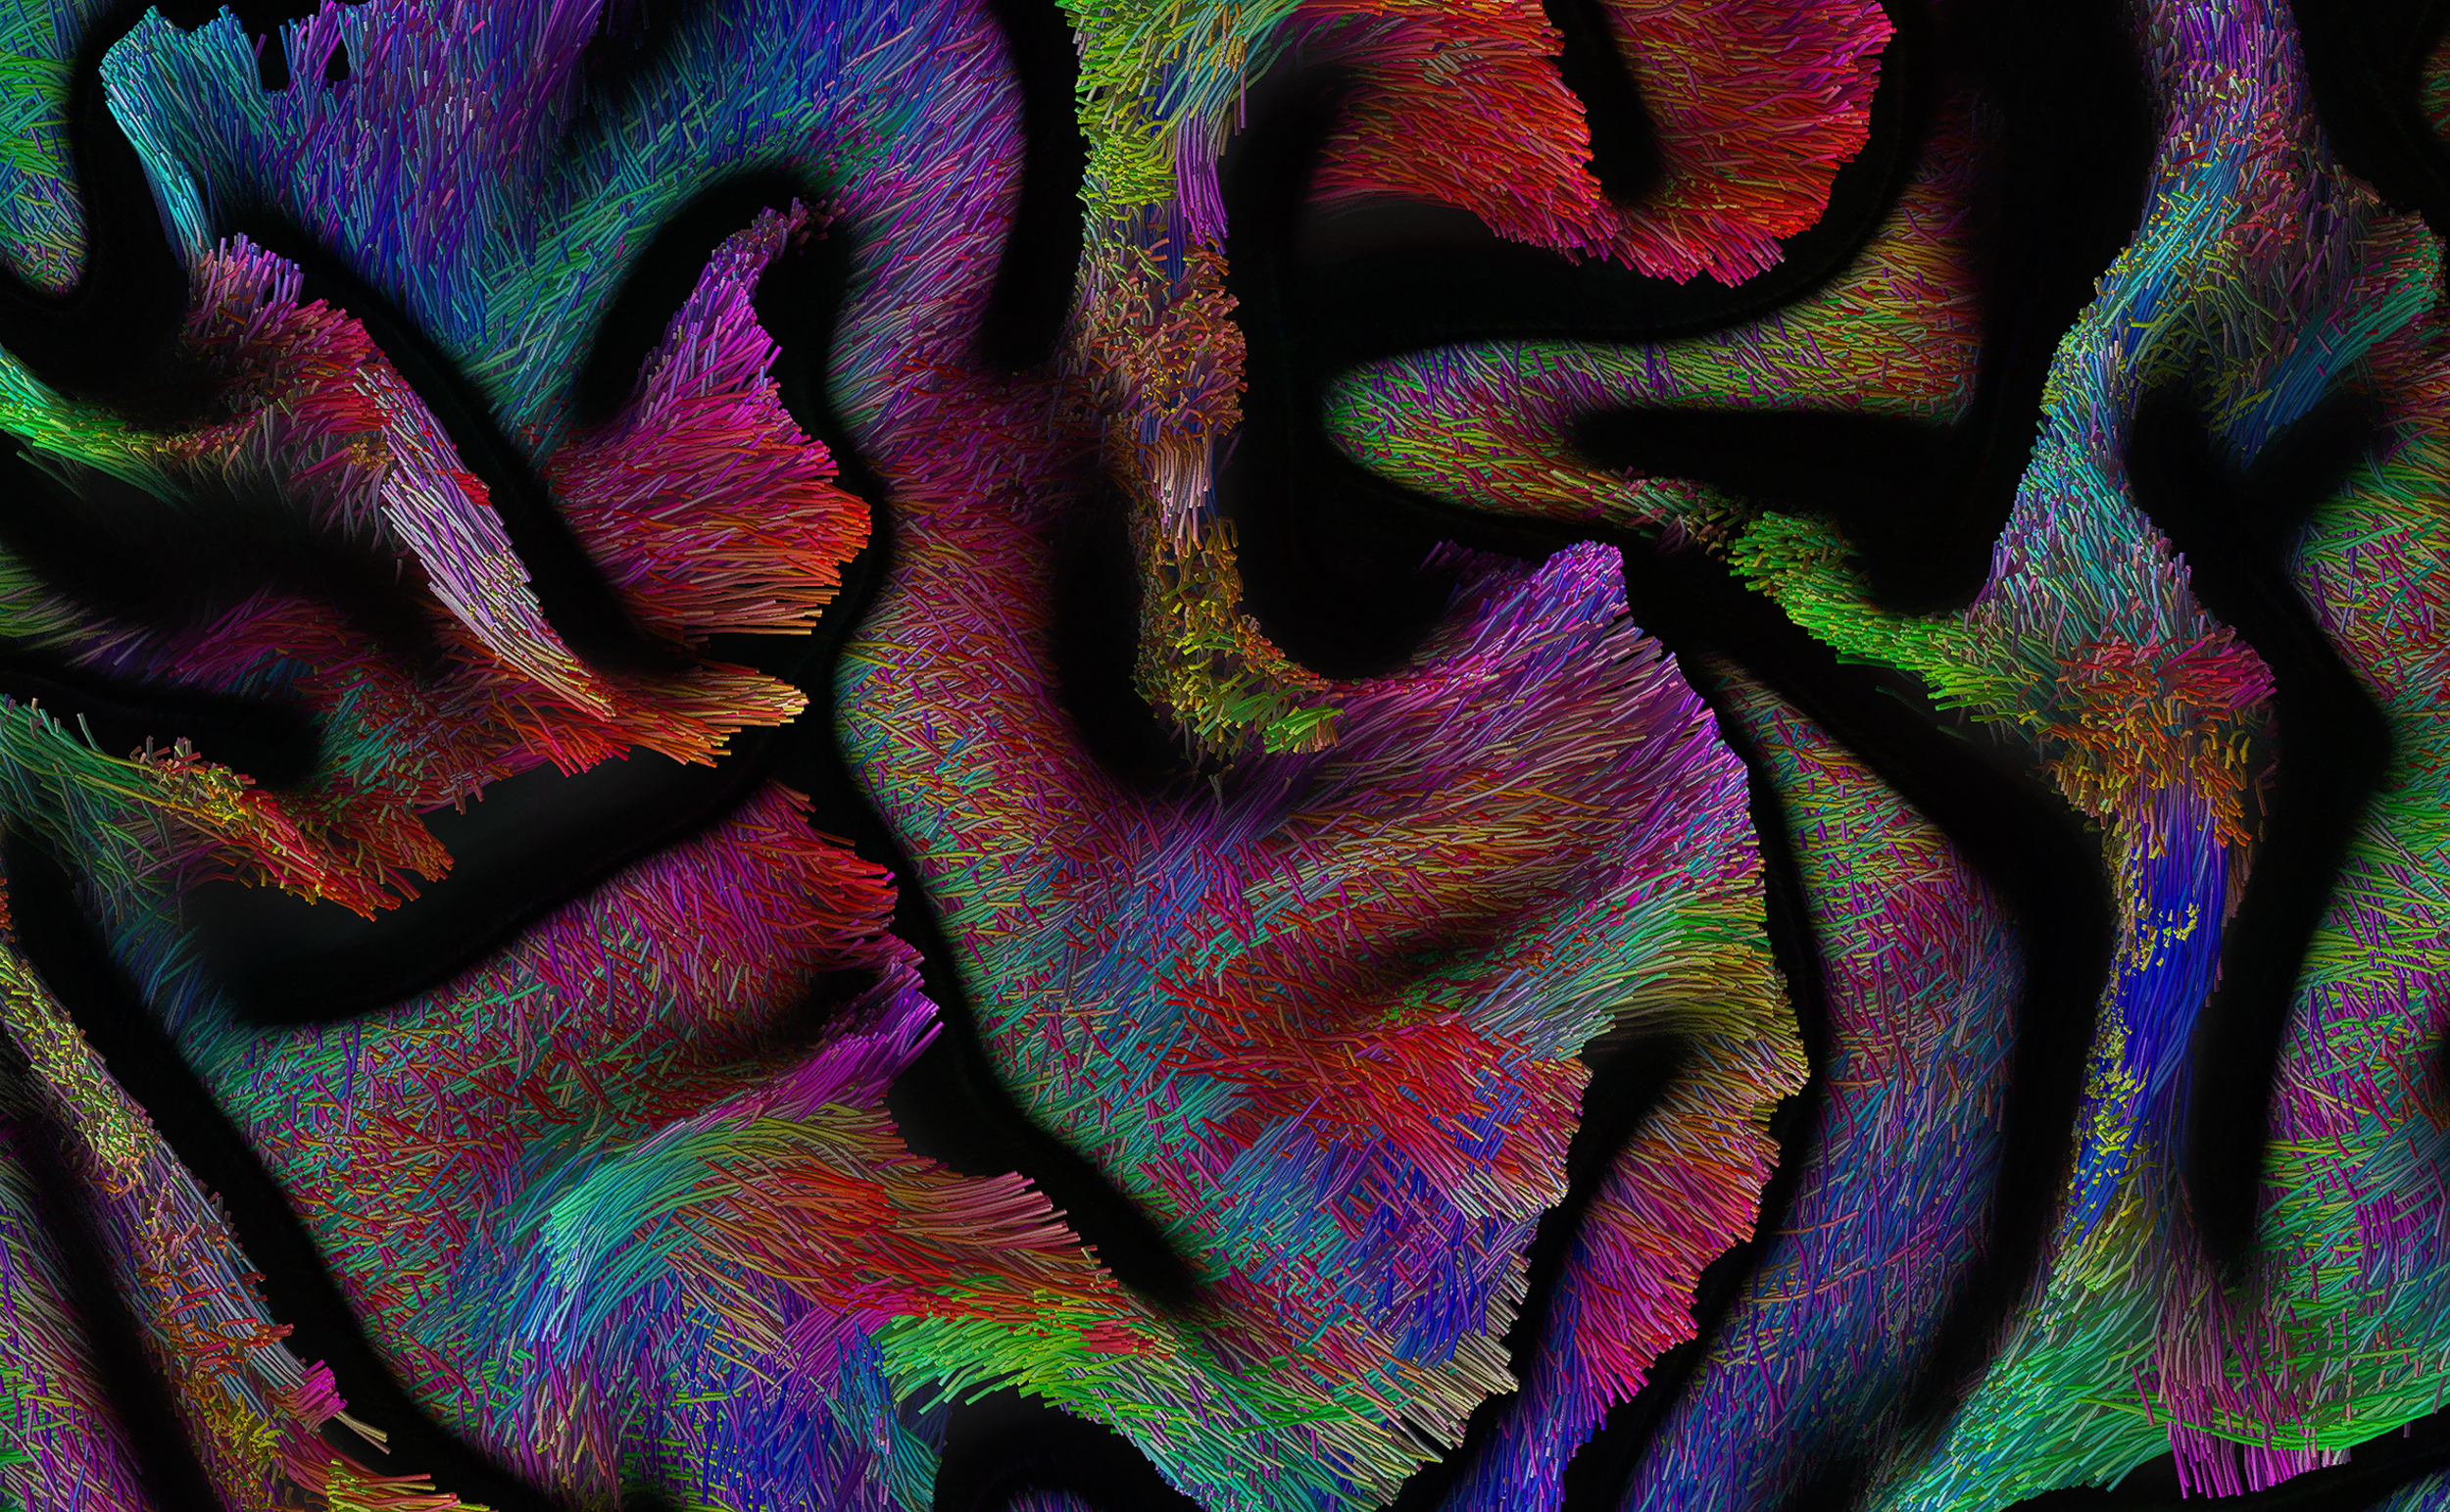

The Adaptive Digital Twin project aims to achieve their goals through four primary strategies. Firstly, we plan to implement a measure that allows real-time probing of effective local and widespread change in whole brain connectivity based on a combination of transcranial magnetic stimulation (TMS) and electroencephalography (EEG). Secondly, we generate high-quality neuroimaging data from brain tumor patients in a joined research project with DFG SPP 2041, which can be used to synthesize digital brain matter using machine-learning algorithms to dramatically increase cohort sizes. thirdly, we refine the correlation analyses of structure-function brain networks with psycholinguistic assessments and real-time mapping during awake surgery. Lastly, we model the effect of different lesions on the level of personalized biophysical brain network models by comparing patient profiles before and after their surgery along with their brain structure information.

In addition, in a further sub-project, we explore the material properties of the brain in relation to neuroimaging in tumor patients, investigating the effects of degeneration, pressure, or stretching mechanisms on brain tissues and the resulting functional consequences, in terms of network and behavior. We use MR-Elastography (MRE) imaging to measure local physical properties of brain matter and add a novel material science perspective to the question of the brain's structure-function relationship.